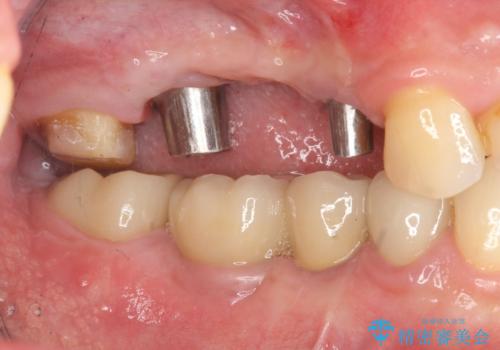

インプラント治療・セラミック治療を含む 全顎的虫歯治療

以上のような問題を、徹底的な虫歯治療、歯周外科、インプラント治療、部分矯正治療、精密根管治療を用いてひとつずつ解決ししっかりと長期的に食事を楽しめるような口腔内環境の再構築を目指します。

インプラント治療の注意事項(リスク・副作用など)

- 外科手術のため、術後に痛みや腫れ、違和感を伴います

- メンテナンスを怠ったり喫煙により、お口の中に大きな悪影響を及ぼすインプラント周囲炎等にかかる可能性があります